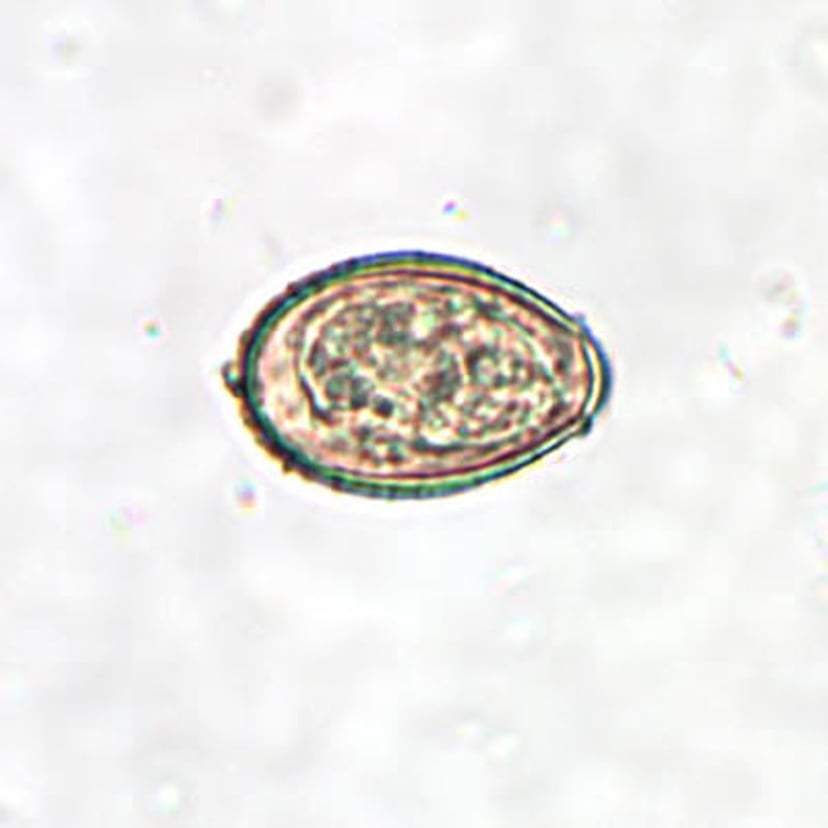

Clonorchis sinensis Egg

C. sinensis eggs are small, ranging in size from 27 to 35 micrometers by 11 to 20 micrometers. The eggs are oval-shaped with a convex operculum (protective covering or lid-like structure) that rests on visible “shoulders” at the smaller end of the egg. Magnification is 400X.